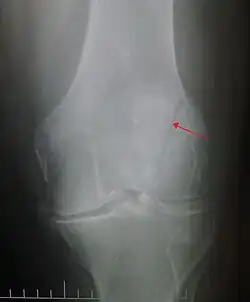

Vertical patella fracture

The patella can break in various ways depending on the way it is injured, and into two or more pieces.[1] Types include transverse, the most common, with one fracture line;[5] marginal; osteochondral; and the rare vertical type, or stellate, where a direct compression force gives rise to a comminuted pattern.[5][7] Patella fractures can be further classified as displaced, where the broken ends of bone do not line up correctly and separate by more than 2mm, or undisplaced and stable where pieces of bone remain in contact with each other.[1][7] If fragments of patella bone stick out from the skin it is known as an open patella fracture, and closed if the overlying skin is intact.[1]